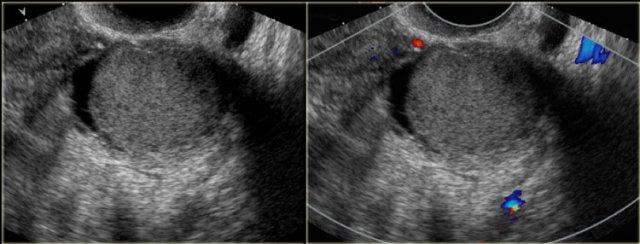

Trường hợp tiếp theo là tổn thương buồng trứng một ngăn, giảm âm nhẹ với hiện tượng tăng âm phía sau.

Không ghi nhận tín hiệu mạch máu bên trong hay ở thành nang trên siêu âm Doppler.

Trên siêu âm, tổn thương này có thể là nang xuất huyết hoặc endometrioma.

Tiếp tục xem hình ảnh MRI.

MRI theo dõi được thực hiện 6 tháng sau.

Các tổn thương tăng tín hiệu trên chuỗi xung T1W.

Tín hiệu sáng vẫn tồn tại trên chuỗi xung ức chế mỡ, xác nhận sự hiện diện của máu.

Có dấu hiệu shading trên T2W phù hợp với tổn thương xuất huyết.

Không có ngấm thuốc.

Mức dịch-dịch trong tổn thương buồng trứng phải cũng xác nhận bản chất dạng nang của tổn thương.

Việc các tổn thương vẫn tồn tại sau 6 tháng làm cho chẩn đoán endometrioma hai bên có khả năng cao hơn nhiều so với nang xuất huyết.